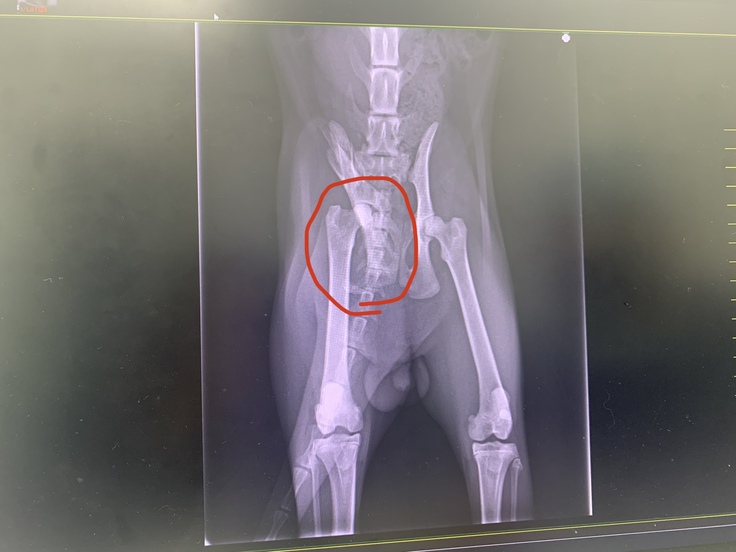

◯5月19日(金)

退院予定でしたが

自力で排泄ができるようにする為

骨盤を広げる手術を行うことに。

↓手術前の写真

術後のレントゲン写真